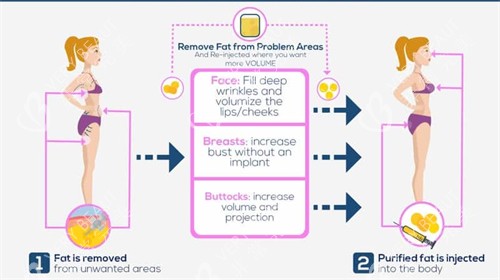

他自创的“脂肪三维护活体系”,从提取、提纯到填充全程把控:取脂时用2.0mm超细钝针,配合“扇形低负压抽取”,减少脂肪细胞破损;提纯时采用“离心+过滤+静置”三重处理,去除油脂、血水等杂质,保留活性高的脂肪颗粒;

填充时用“多点、分层、微量”注射法,将脂肪均匀注入乳腺后间隙和皮下层,避免堆积形成结节,不少求美者反馈术后3个月成活率高,基本一次就能达到理想罩杯。